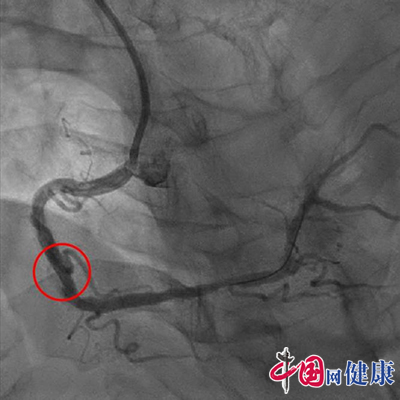

术后血管恢复血流

准分子激光消蚀导管、旋磨导管、双导丝球囊、切割球囊……冠脉介入治疗团队做好充分的术前准备,按预定方案,罗礼云副主任医师行准分子激光斑块消蚀术联合旋磨术,顺利开通了患者的血管,植入支架效果理想,术后患者心绞痛症状随即缓解,现已康复出院。